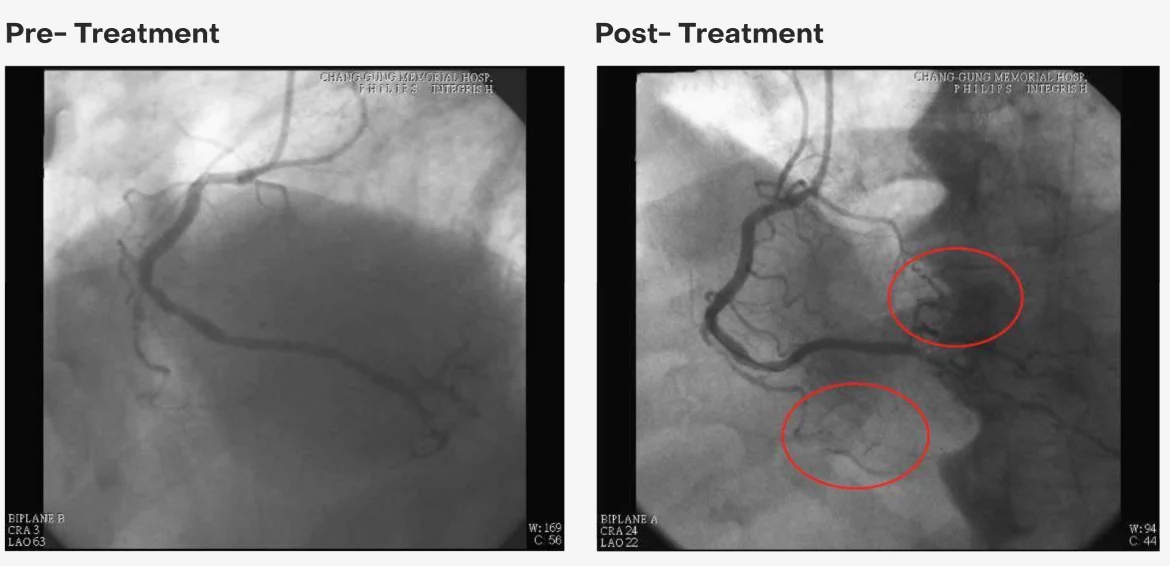

Before and After Treatment